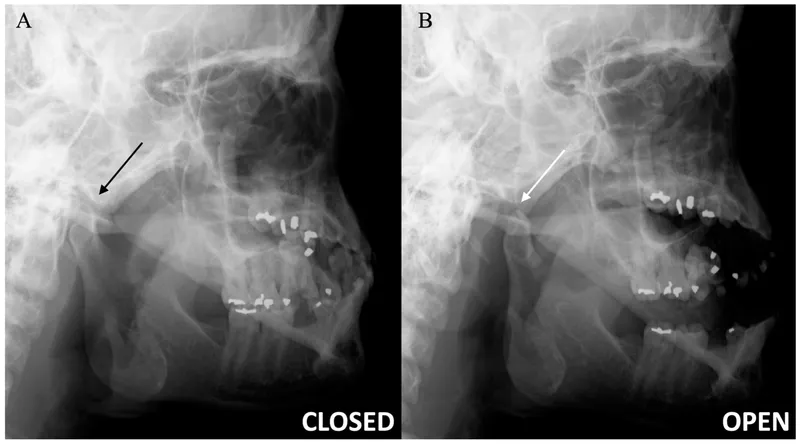

Temporomandibular Joint (TMJ):

- Synovial joint: Mandibular condyle & Temporal bone (fossa, tubercle).

- Movements: Elevation, depression, protrusion, retraction, lateral.